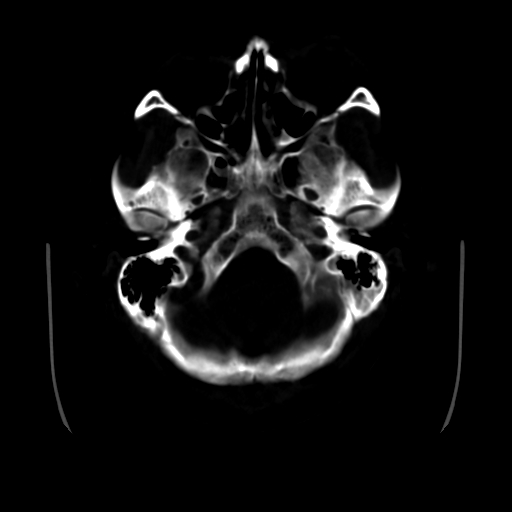

男,51岁,头外伤一小时,呕吐两次。

1)左侧中颅窝蝶骨翼后方硬膜外血肿。2)左侧颞顶部硬膜下血肿。3)蛛网膜下腔出血。4)左侧筛窦及双侧蝶窦炎症(或积血)。5)左侧额部头皮软组织肿胀。